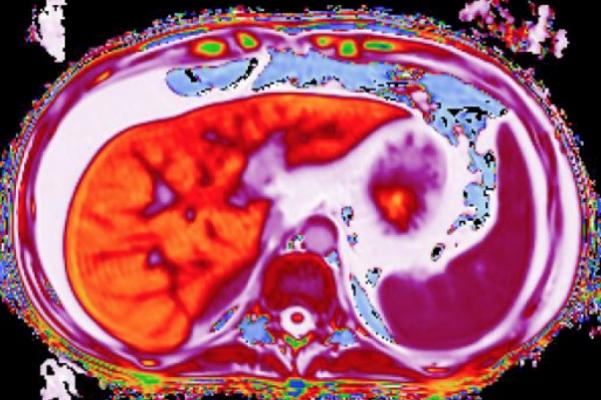

LiverMultiScan uses a painless, 15-minute MRI scan which characterizes liver tissue. Developed by Perspectum Diagnostics in Oxford, U.K., this test already has regulatory clearance for use in adults to aid physicians in diagnosing early liver disease.

LiverMultiscan is now installed in medical institutions on three continents. Used in the clinical management of patients with chronic liver disease, the technology offers a quantitative liver assessment in a safe, non-invasive 15-minute MRI scan. Analysis is based on assessment of native properties of liver tissue, accurate measurement of liver fat and other metrics. The technology is currently being used to assess primary endpoints in clinical trials for investigational therapies to treat non-alcoholic fatty liver disease (NAFLD) and non-alcoholic steatohepatitis (NASH).